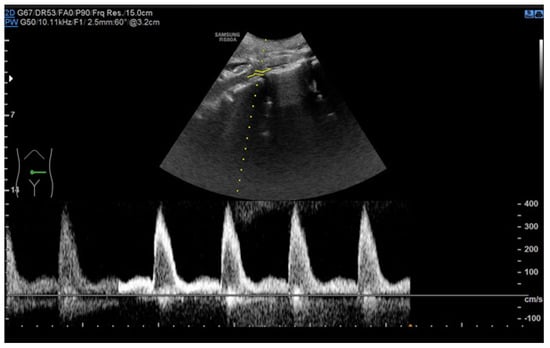

6.1. Ultrasound

- Drelich-Zbroja, A. Polish Society of Ultrasonography Standards—Update: Ultrasound Examination of Renal Arteries. J. Ultrason. 2014, 14, 297–305. [Google Scholar] [CrossRef]

- Stryczyński, Ł. Doppler ultrasound of renal arteries. Arter. Hypertens. Pract. 2022, 8, 186–199. [Google Scholar]

| Normal Value | Parameter |

|---|---|

| 100 cm/s * | PSV (peak systolic velocity) in artery trunk |

| 0.8–1.0 | RAR (renal aortic ratio) in artery trunk |

| ≤70 ms | AT (acceleration time) in intrarenal branches |

| 0.5–0.8 | RI (resistance index) in intrarenal branches |

| 0.78–1.33 | PI (pulsatility index) in intrarenal branches |

| >3 m/s2 | AI (acceleration index) in intrarenal branches |